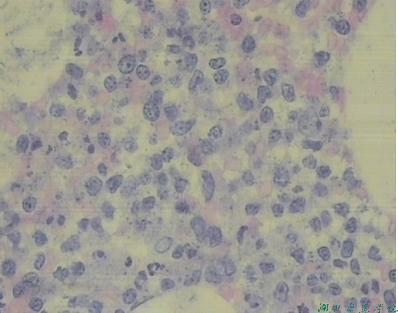

骨髓细胞学检查

骨髓增生明显活跃,幼稚淋巴细胞占54.5%,符合幼稚淋巴细胞白血病。

骨髓病理:符合幼淋巴细胞白血病。

骨髓象:增生明显活跃,有核仁的幼淋巴细胞占17%-80%,其他系增生受抑。